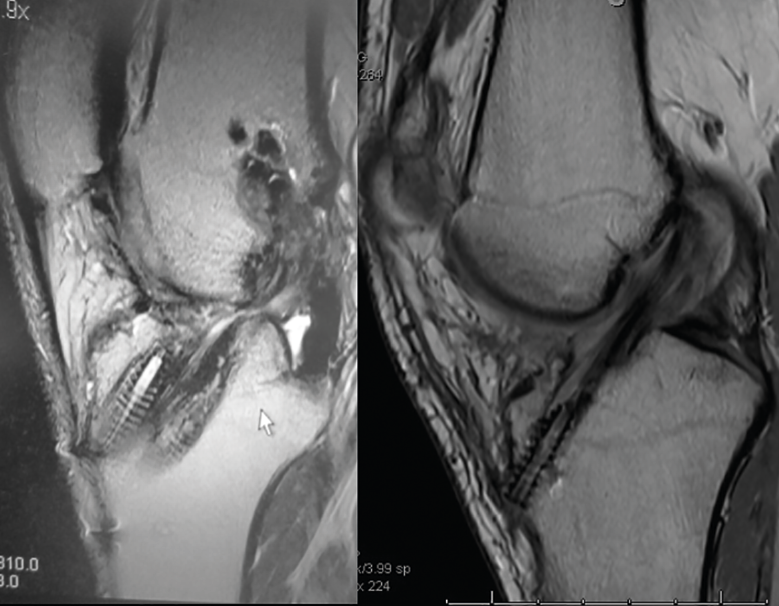

La RM será útil para conocer la situación de las partes blandas intraarticulares: restos de la plastia del LCA previa, valoración de posibles lesiones asociadas, defectos meniscales previos, lesiones condrales, etc. (Figura 5).

Figura 5. El estudio mediante resonancia magnética permite evaluar la situación de la plastia del ligamento cruzado anterior, así como del resto de las estructuras intraarticulares.